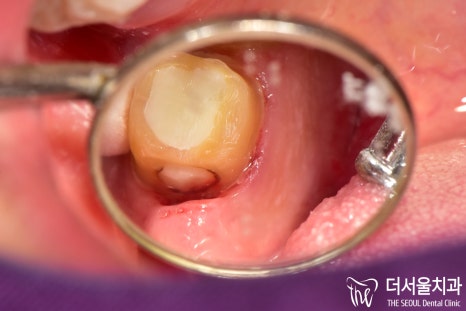

자, 일단 구강 내 상태가 어떤지

직접 확인을 해봐야겠죠?

더서울에서 확인을 해보니

문제는 한곳이 아니었습니다.

일단 하나씩 살펴볼까요?

검게 물들어 있는 것이 보입니다.

아마 치관을 넘어 치근에도

영향을 끼치지 않았을까 판단이 되네요.

뭐 위생관리가 잘 된다면 다행이지만,

맨 뒤쪽에 위치해있기 때문에

스스로 청결한 관리를 하는 게 쉽지 않죠.

반대쪽을 살펴보겠습니다.

음 이곳의 문제도 꽤 심각했습니다.

아무래도 두 곳 모두 간단한 방법으로는

개선할 수 없겠다는 판단이 들었습니다.